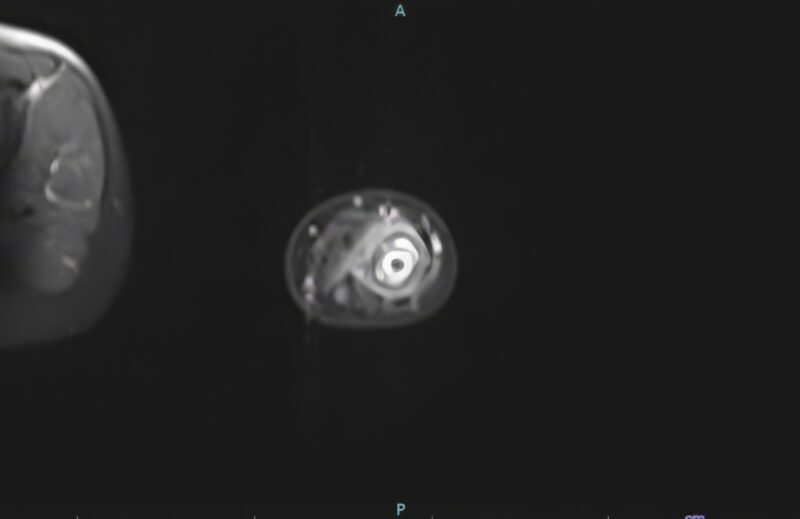

In SCD, the radiological findings in diseased bones, which include bone infarction and edema as a result of limited blood supply and recurrent VOCs, might trigger an inflammatory response locally and cause subperiosteal edema, which can be misinterpreted as infection (Figures 3 and 4). The breakdown of the cortex (Figure 5) by the pus indicates the acuity of the inflammatory process in the bone due to neutrophilic infiltration in response to bone marrow invasion by microorganisms, which indicates OM.

Figure 5: Cortical break

Those radiological findings were grouped as less probable OM (probable), highly probable OM (definitive), and equivocal (suspected)9. The images were reviewed independently by two radiologists, and they agreed that the presence of cortical destruction was suggestive of OM, while the presence of bone edema, infarction, and subperiosteal edema was more in favor of VOC. The presence of the periosteal collection was equivocal and needed a clinical correlation for a definitive diagnosis of OM vs VOC.